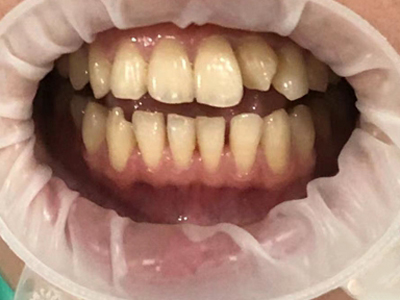

牙龈退缩上排多颗牙的牙根暴露图

牙龈退缩导致上排多颗牙齿的牙龈回缩,部分牙根暴露在外,伴有牙齿松动、口臭等症状,是由于牙周炎、局部受力过大等因素导致。